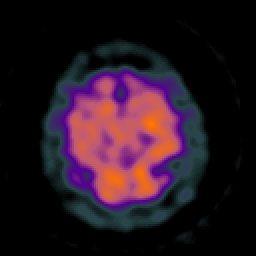

Huntington's Chorea, MR -- Slice #17

[Home][Help][Clinical] Slice 17